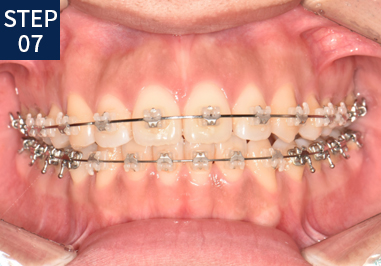

당신만을 위한 치아교정 1:1 프로세스

• 기초 조사 및 상담

• X-RAY/구강/안면촬영

• 치열을 위한 인상채득

• 분석 및 치료계획 수립

• 진단 및 상담

• 장치 장착, 치료

• 주기적 내원

• 장치제거 및 유지장치 장착

• 유지 및 사후관리